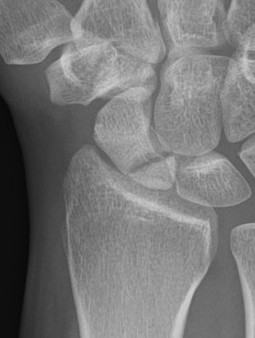

Scaphoid waist fracture 1 mm displaced

Scaphoid fracture with significant displacement

Scaphoid proximal pole fracture